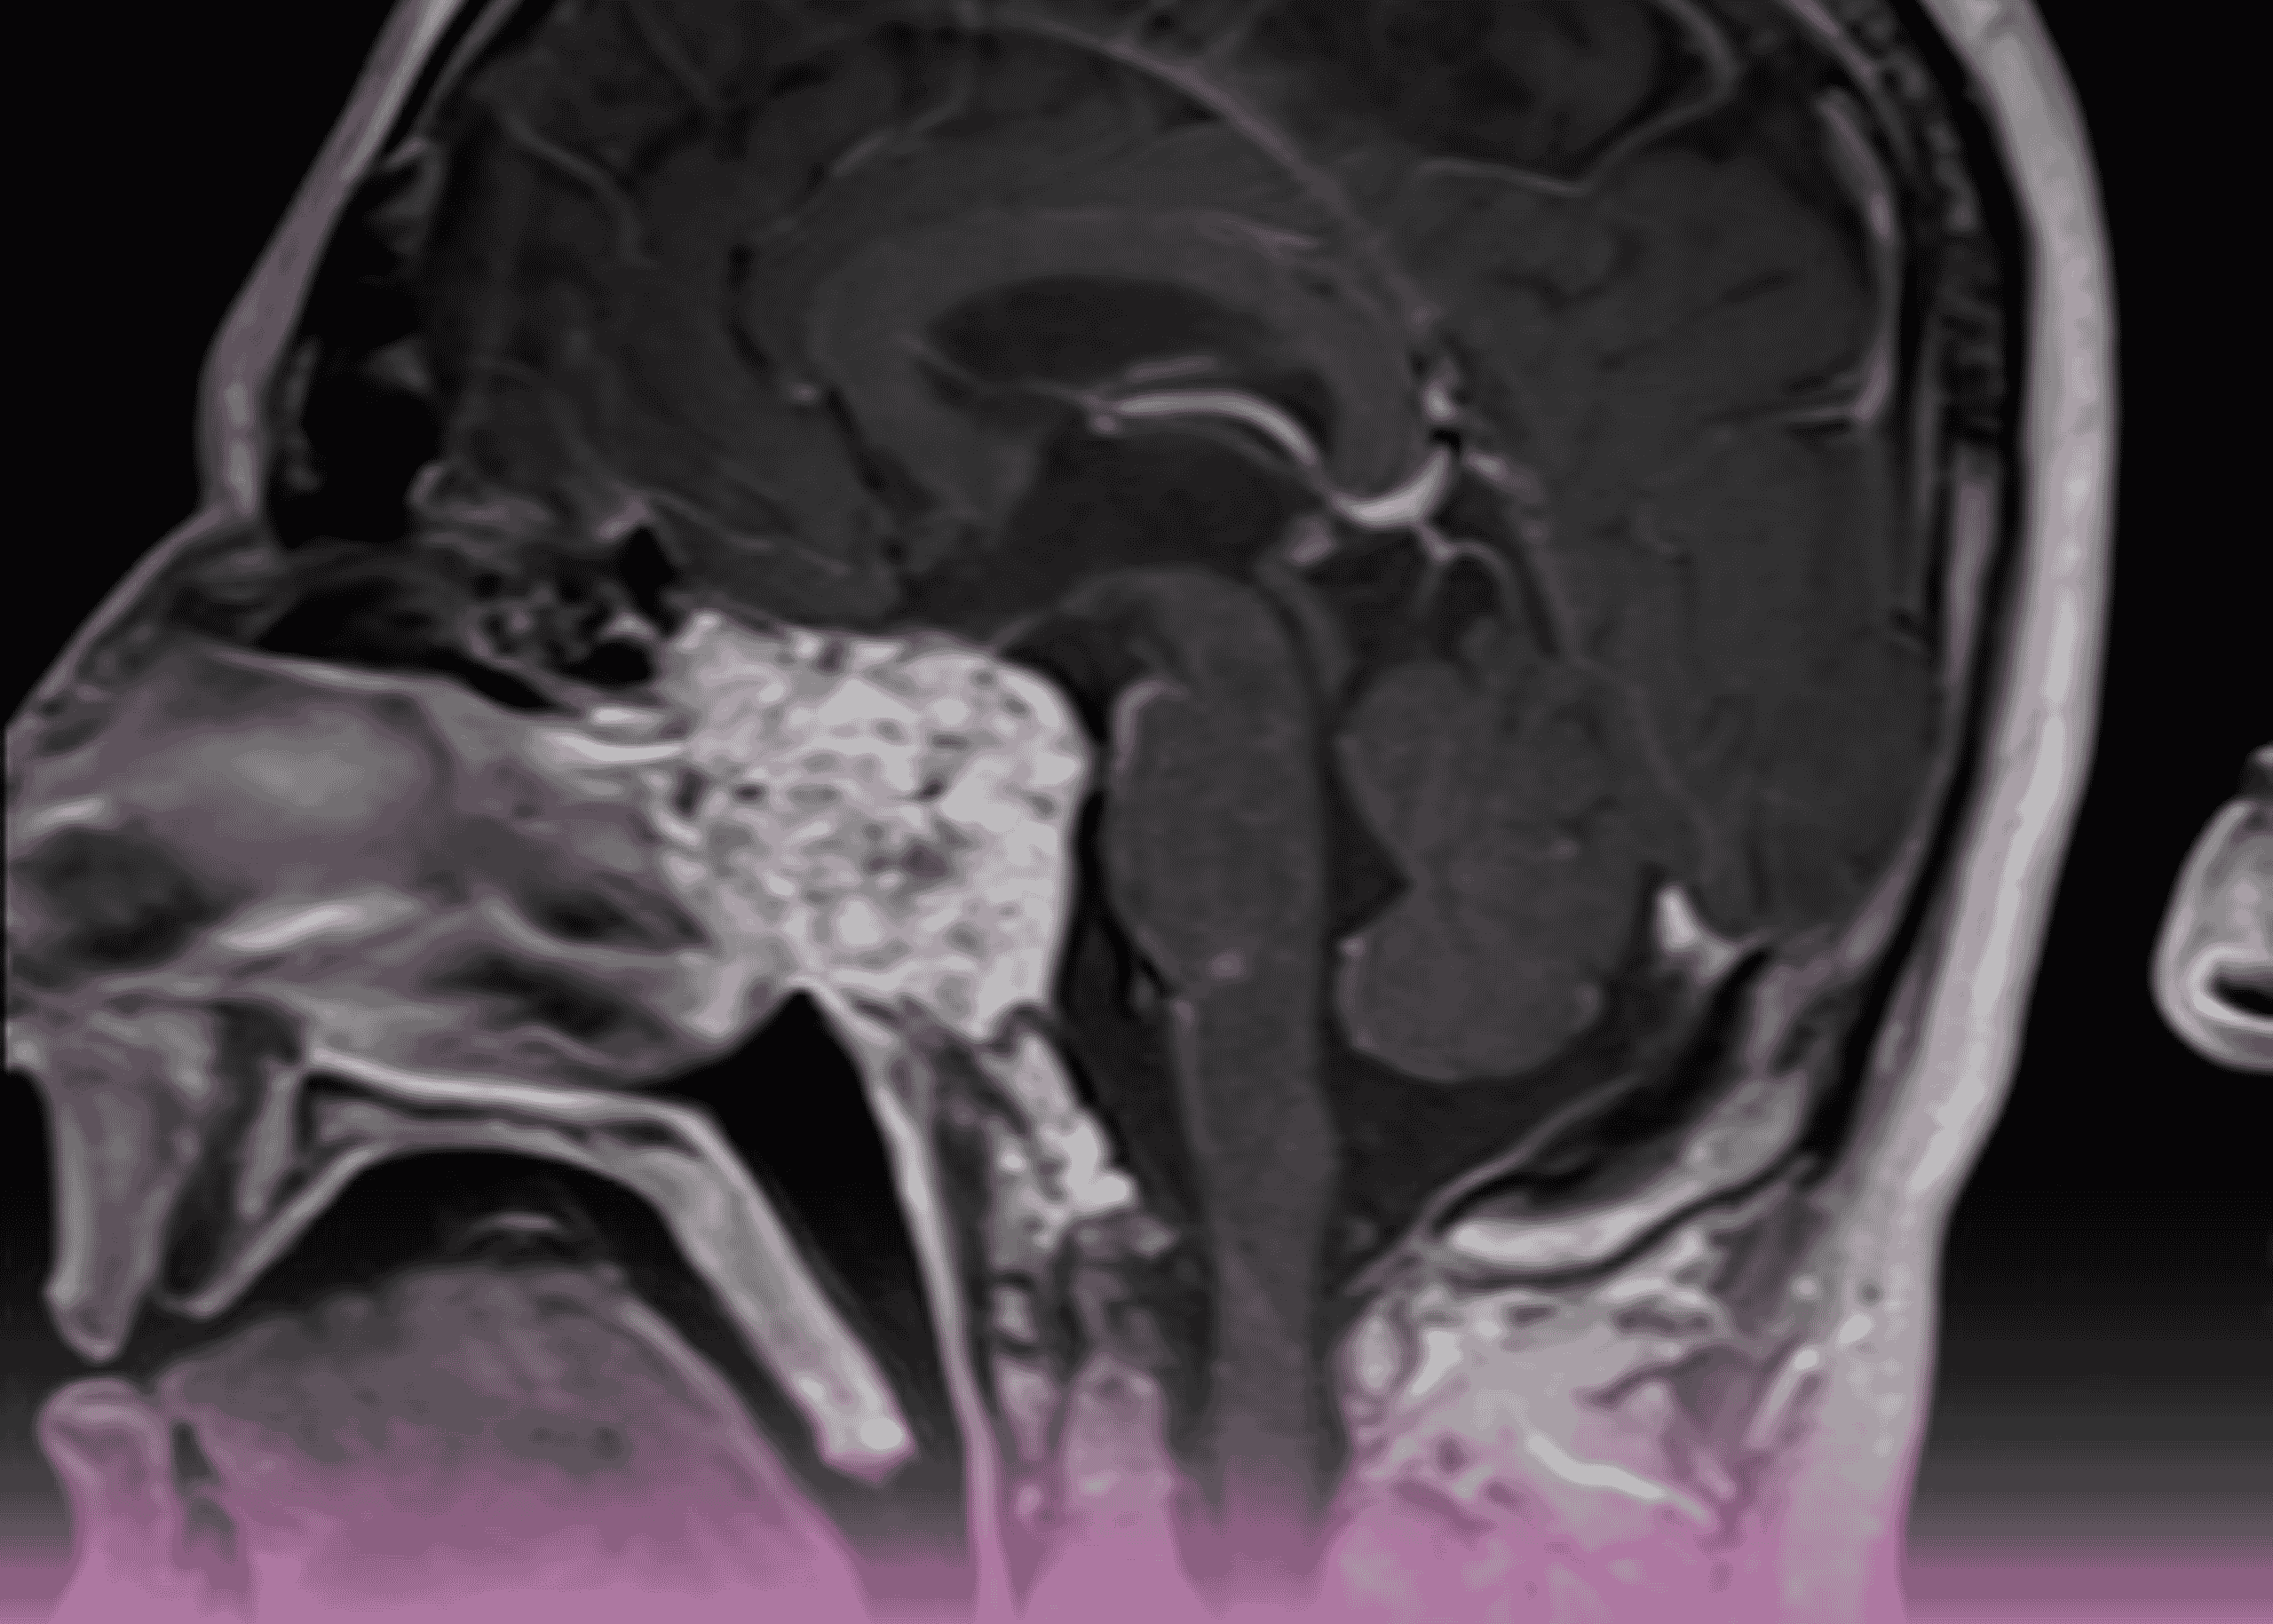

ورم كلايفال كوردوما: التدبير الجراحي المتقدم بالمنظار لورم نادر في قاعدة الجمجمة

مقدمة أورام قاعدة الجمجمة تمثل بعضاً من أكثر الحالات تحدياً في جراحة